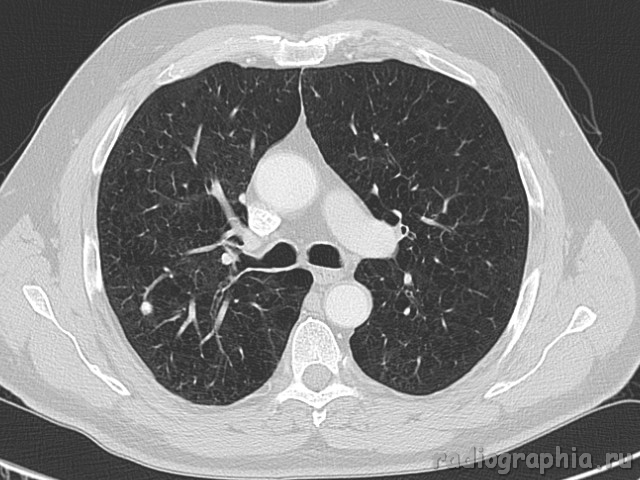

Одиночный узел правого лёгкого.

На рутинном снимке ОГК, был выявлен одиночный узел; по протоколу выполнили КТ. Какое было бы ваше заключение; и как бы Вы поступили если у вас нет возможности выполнять КТ?